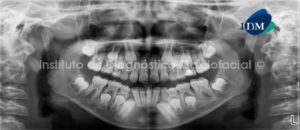

Paciente masculino de 47 años de edad es referido al Instituto de Diagnóstico Maxilofacial para la evaluación y plan de tratamiento correspondiente a la rehabilitación de toda la boca. A la evaluación de la radiografía panorámica (Fig. 1) se aprecia el marcado aplanamiento de la vertiente anterosuperior del cóndilo mandibular del lado derecho, así mismo se observan algunas ausencias dentarias y restos radiculares, así como la pérdida de estructura dentaria a nivel de bordes incisales y caras oclusales. Notese la perdida de estructura dentaria a nivel de caras interproximales, donde se aprecia la marcada disminución del espesor del esmalte, dando un aspecto de dientes tallados para la colocación de prótesis fijas.